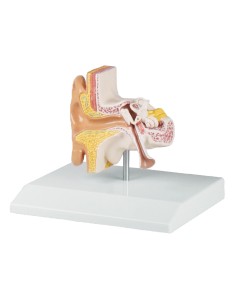

3B Modèle anatomique scientifique des osselets de l'oreille, E13

3B Modèle anatomique scientifique des osselets de l'oreille, 20 fois agrandi comme un os.